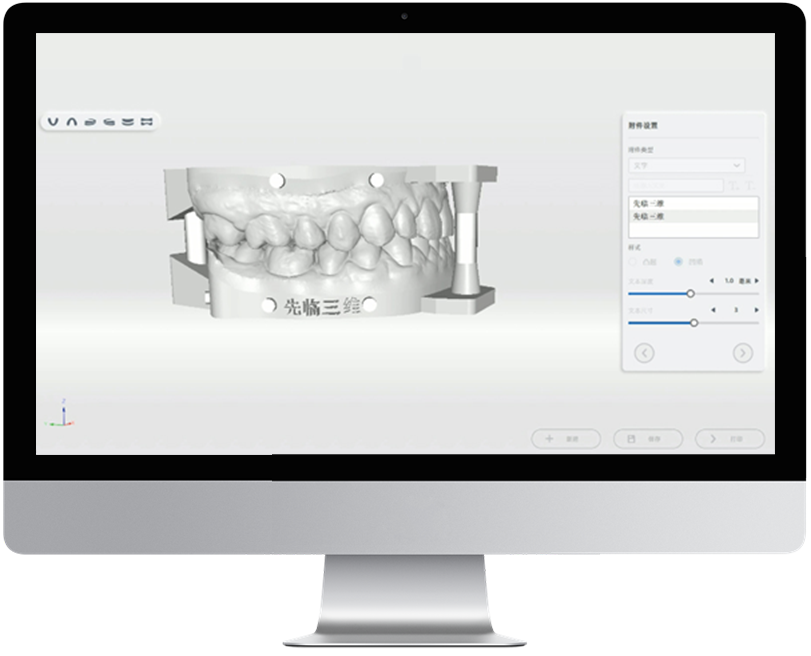

正畸模擬

效果預覽 完美預定

智能識別自動分牙、排牙

口掃數據直接輸出正畸模擬

生成二維碼分享

口掃數據直接輸出正畸模擬

生成二維碼分享

*口腔檢查報告、正畸模擬、一鍵打印為附加選購模塊非標準功能配置,詳情請咨詢區域銷售。

口掃打印一體化

集成AccuDesign模型編輯工具,支持快速封底、抽殼、加字、排溢孔、智能添加頜架等操作。

支持在椅旁直接打印患者口內數據,輔助醫患達成良好的診療溝通。

支持在椅旁直接打印患者口內數據,輔助醫患達成良好的診療溝通。

*口腔檢查報告、正畸模擬、一鍵打印為附加選購模塊非標準功能配置,詳情請咨詢區域銷售。